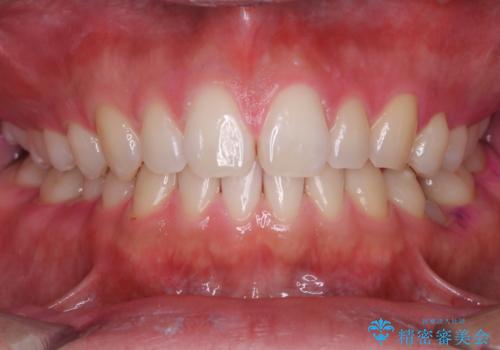

親知らずを抜いて1週間後にPMTC 歯のクリーニング

- 親知らずの抜歯後の約1週間後に抜糸(縫った部分の糸とり)で来院されました。その際、抜歯後は傷口が怖くて歯磨きが上手くできず、汚れや口臭が気になるためクリーニングも希望されました。

抜歯後は多少出血したり、違和感や痛みを感じたりすることがあります。そのため親知らずを抜いたり、外科的な処置をするといつも通りの歯磨きがしづらくなります。また、傷口の周りが心配で、歯ブラシをするのが怖くなるものです。抜歯後落ち着いたら、歯科医院にて専門の機械を使用しクリーニングをすることがおすすめです。抜歯前や後にPMTCを行うことで、お口の中の健康維持につながり、その後の感染・腫れ・口臭予防などになります。

親知らず抜歯後正常に治癒が進んでいれば1週間後から可能です。